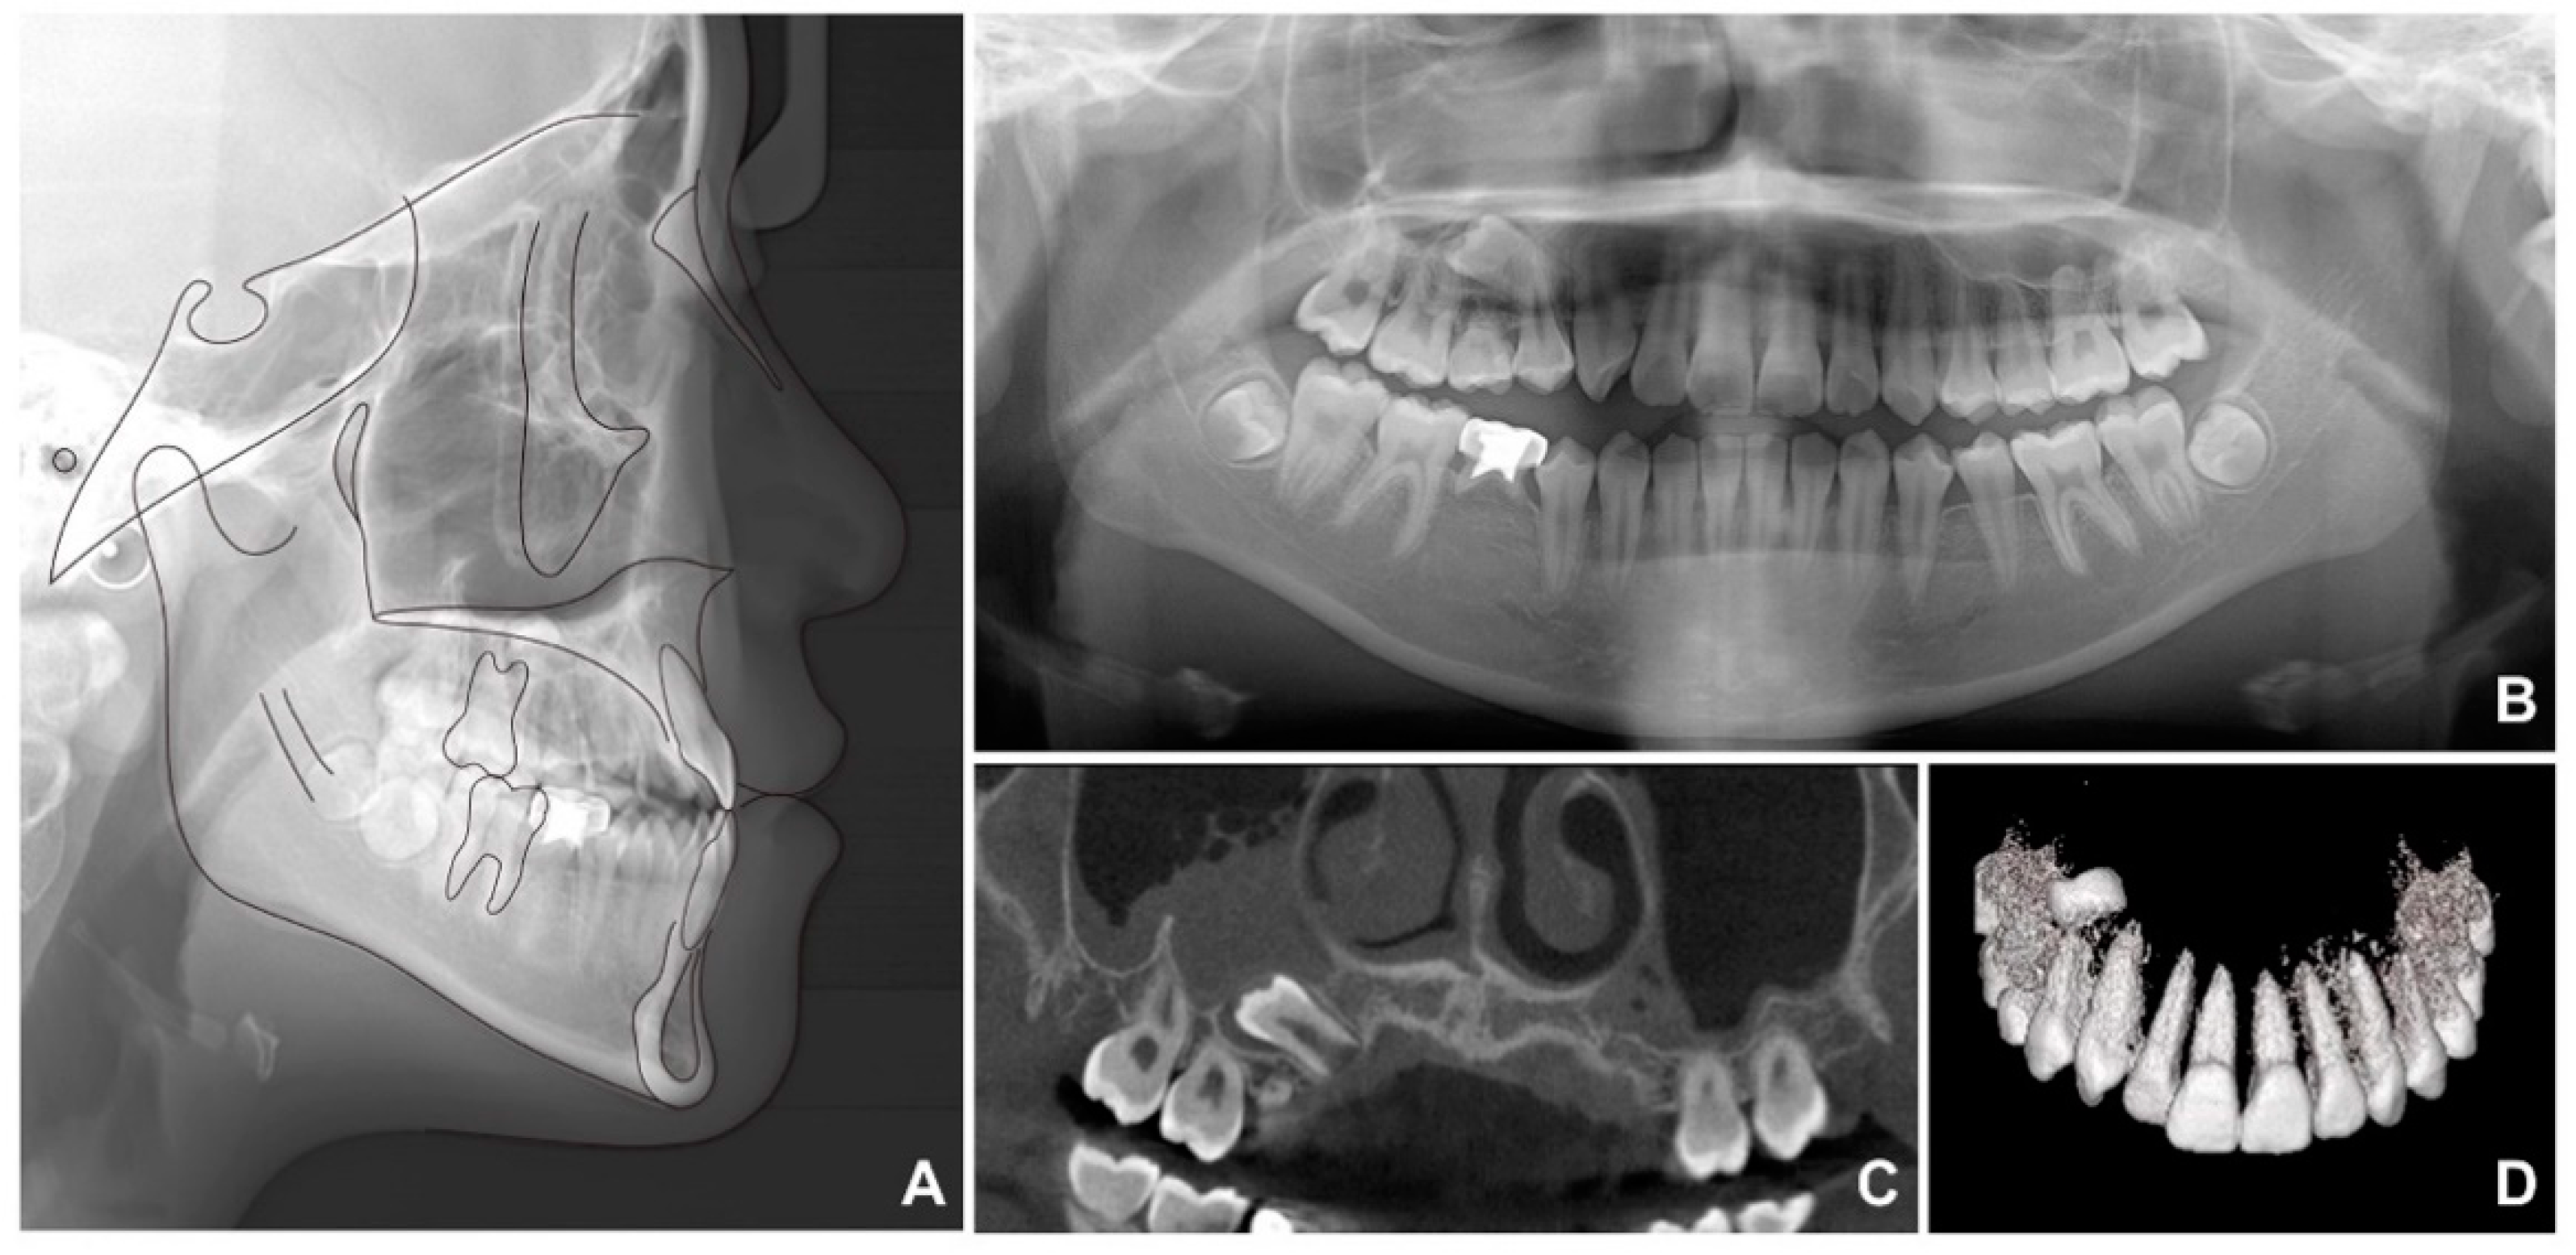

When superimposition analysis was performed with pre- and post-treatment radiographs, a small amount of growth was observed in the mandible (Figure 8). Protraction of the mandibular right molars and retraction of the mandibular anterior teeth were successful after extraction of the mandibular primary second molars.

Figure 8. Superimposition before and after treatment: (A) total; (B) maxilla; (C) mandible.